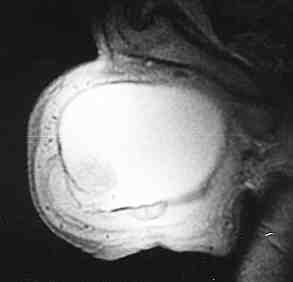

fig. 1

Figura 1.- RMN: Estructura ovoidea de 8X8X7 en hemiescroto izquierdo que presenta gran homogeneidad, con hiperintensidad, salvo por pequeño polo anteroinferior que es de menor intensidad. Pared escrotal muy engrosada.